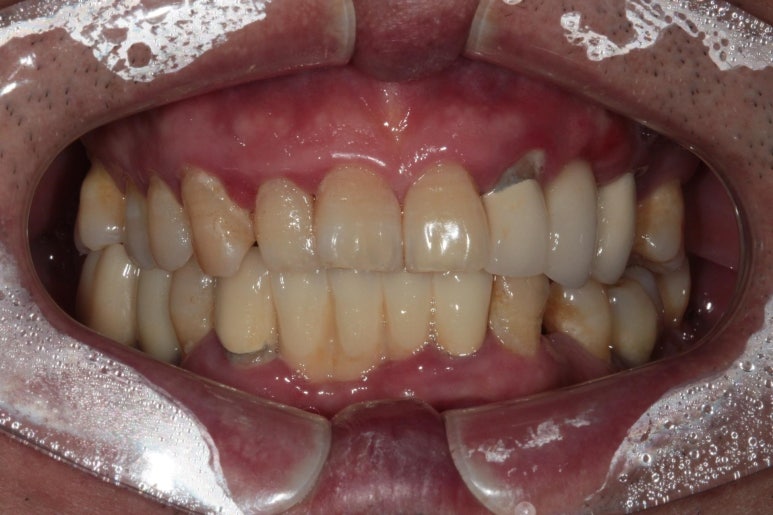

저희 병원에 오셨던 60대 남자 환자분입니다.

딱 봐도 구강위생상태가 좋지 않습니다...

잘 보시면 적절히 관리되지 않아 다수 축적되어있는 치태와 치석들을 쉽게 보실 수 있죠.

아~ 잇몸이 좋지 않았습니다. 그래서 스케일링과 잇몸치료 그리고 필요한 치아를 뽑고 임플란트 하기를 권해드렸죠. 이 분이 3년만에 저희 병원에 다시 오셨는데요.